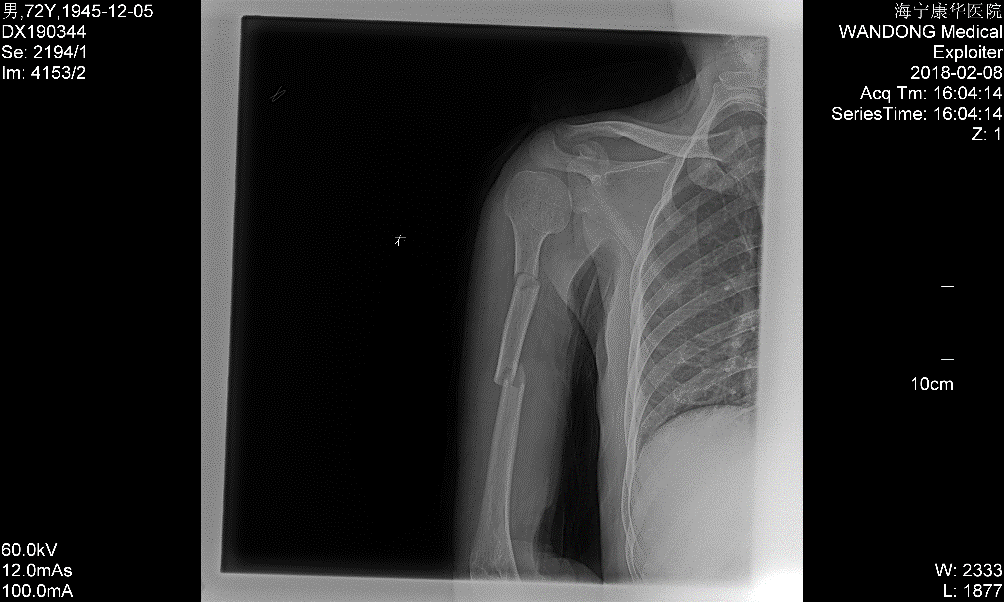

一周后,X片显示骨折位置同前,并没有出现移位情况,李先生跟李大伯都面露喜色,陈主任也略略松了口气,又重新为李大伯的外固定进行了调整加固。